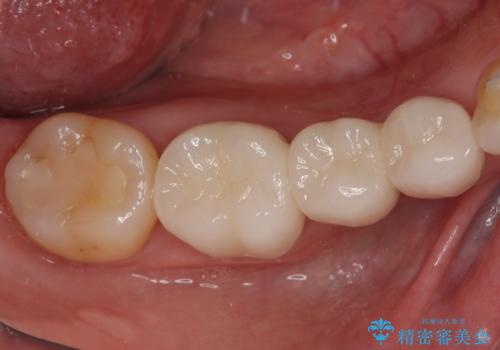

矯正治療自体はインビザラインで満足のいく仕上がりとなりました。

前歯は根管治療が必要となり、元々舌側に入り込んでいた左上2番目の歯は歯周外科処置により歯肉ラインを整えることとしました。

欠損部位は傾斜歯軸を起き上がらせることができたため、オールセラミッククブリッジにて補綴治療を行いました。

全顎的に満足のいく仕上がりとなりました。